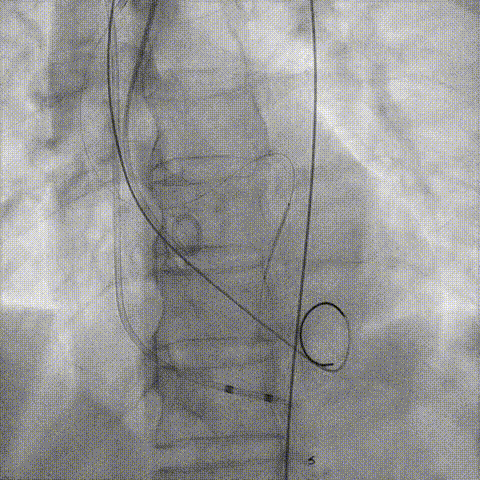

造影评估

支架内后扩张

冠脉造影

根部造影

最终结果